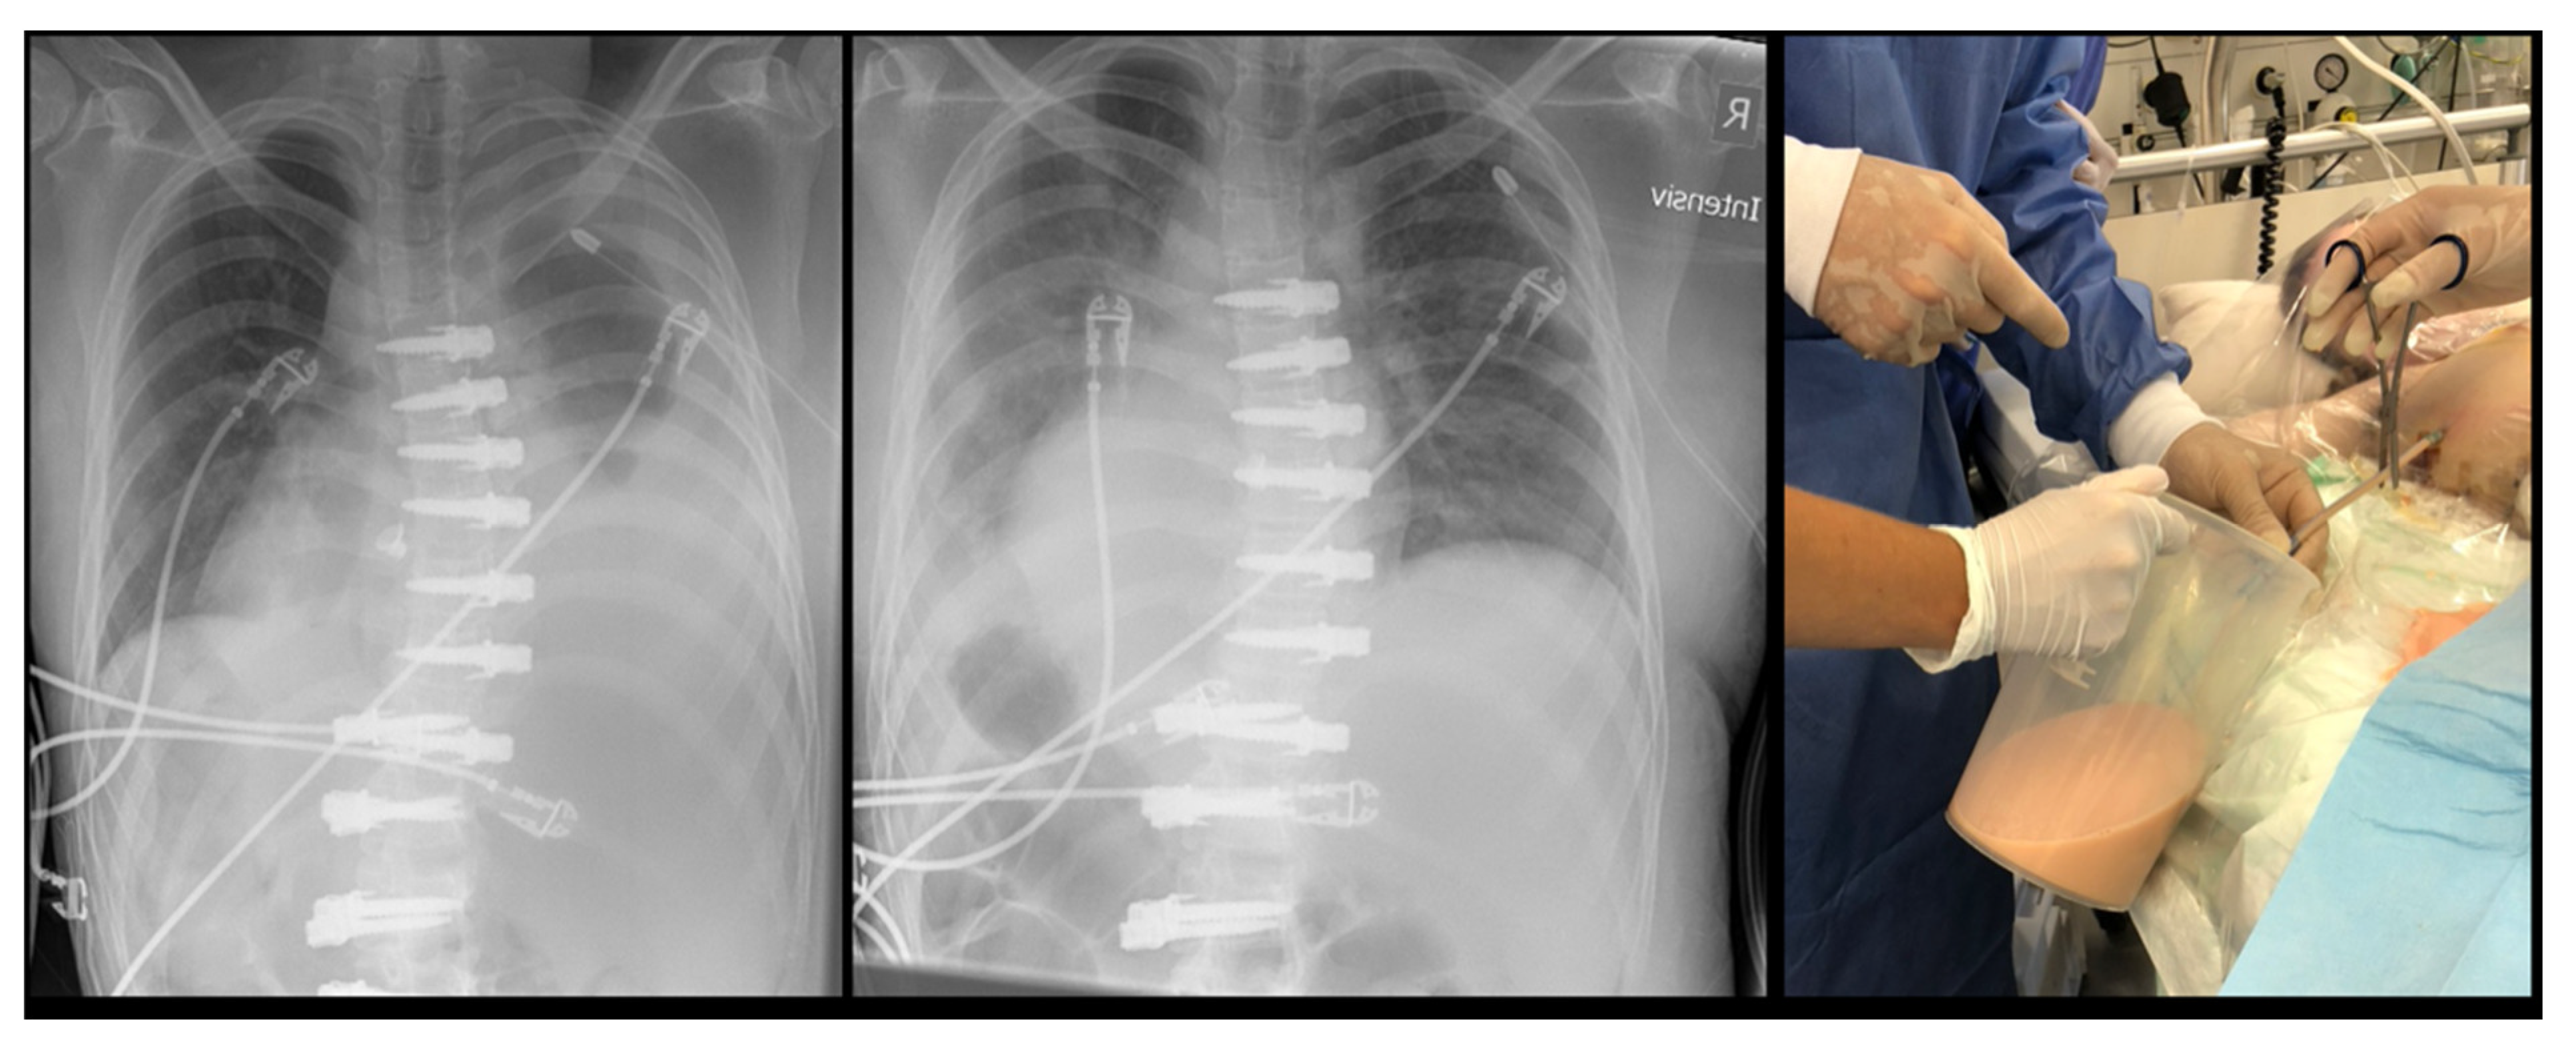

Figure 4.

Patient from Figure 3. (Left) Chest radiograph after drainage of 1 L; (Middle) Chest radiograph after drainage of 2.5 L; (Right) Macroscopic appearance of orange-milky chylos.